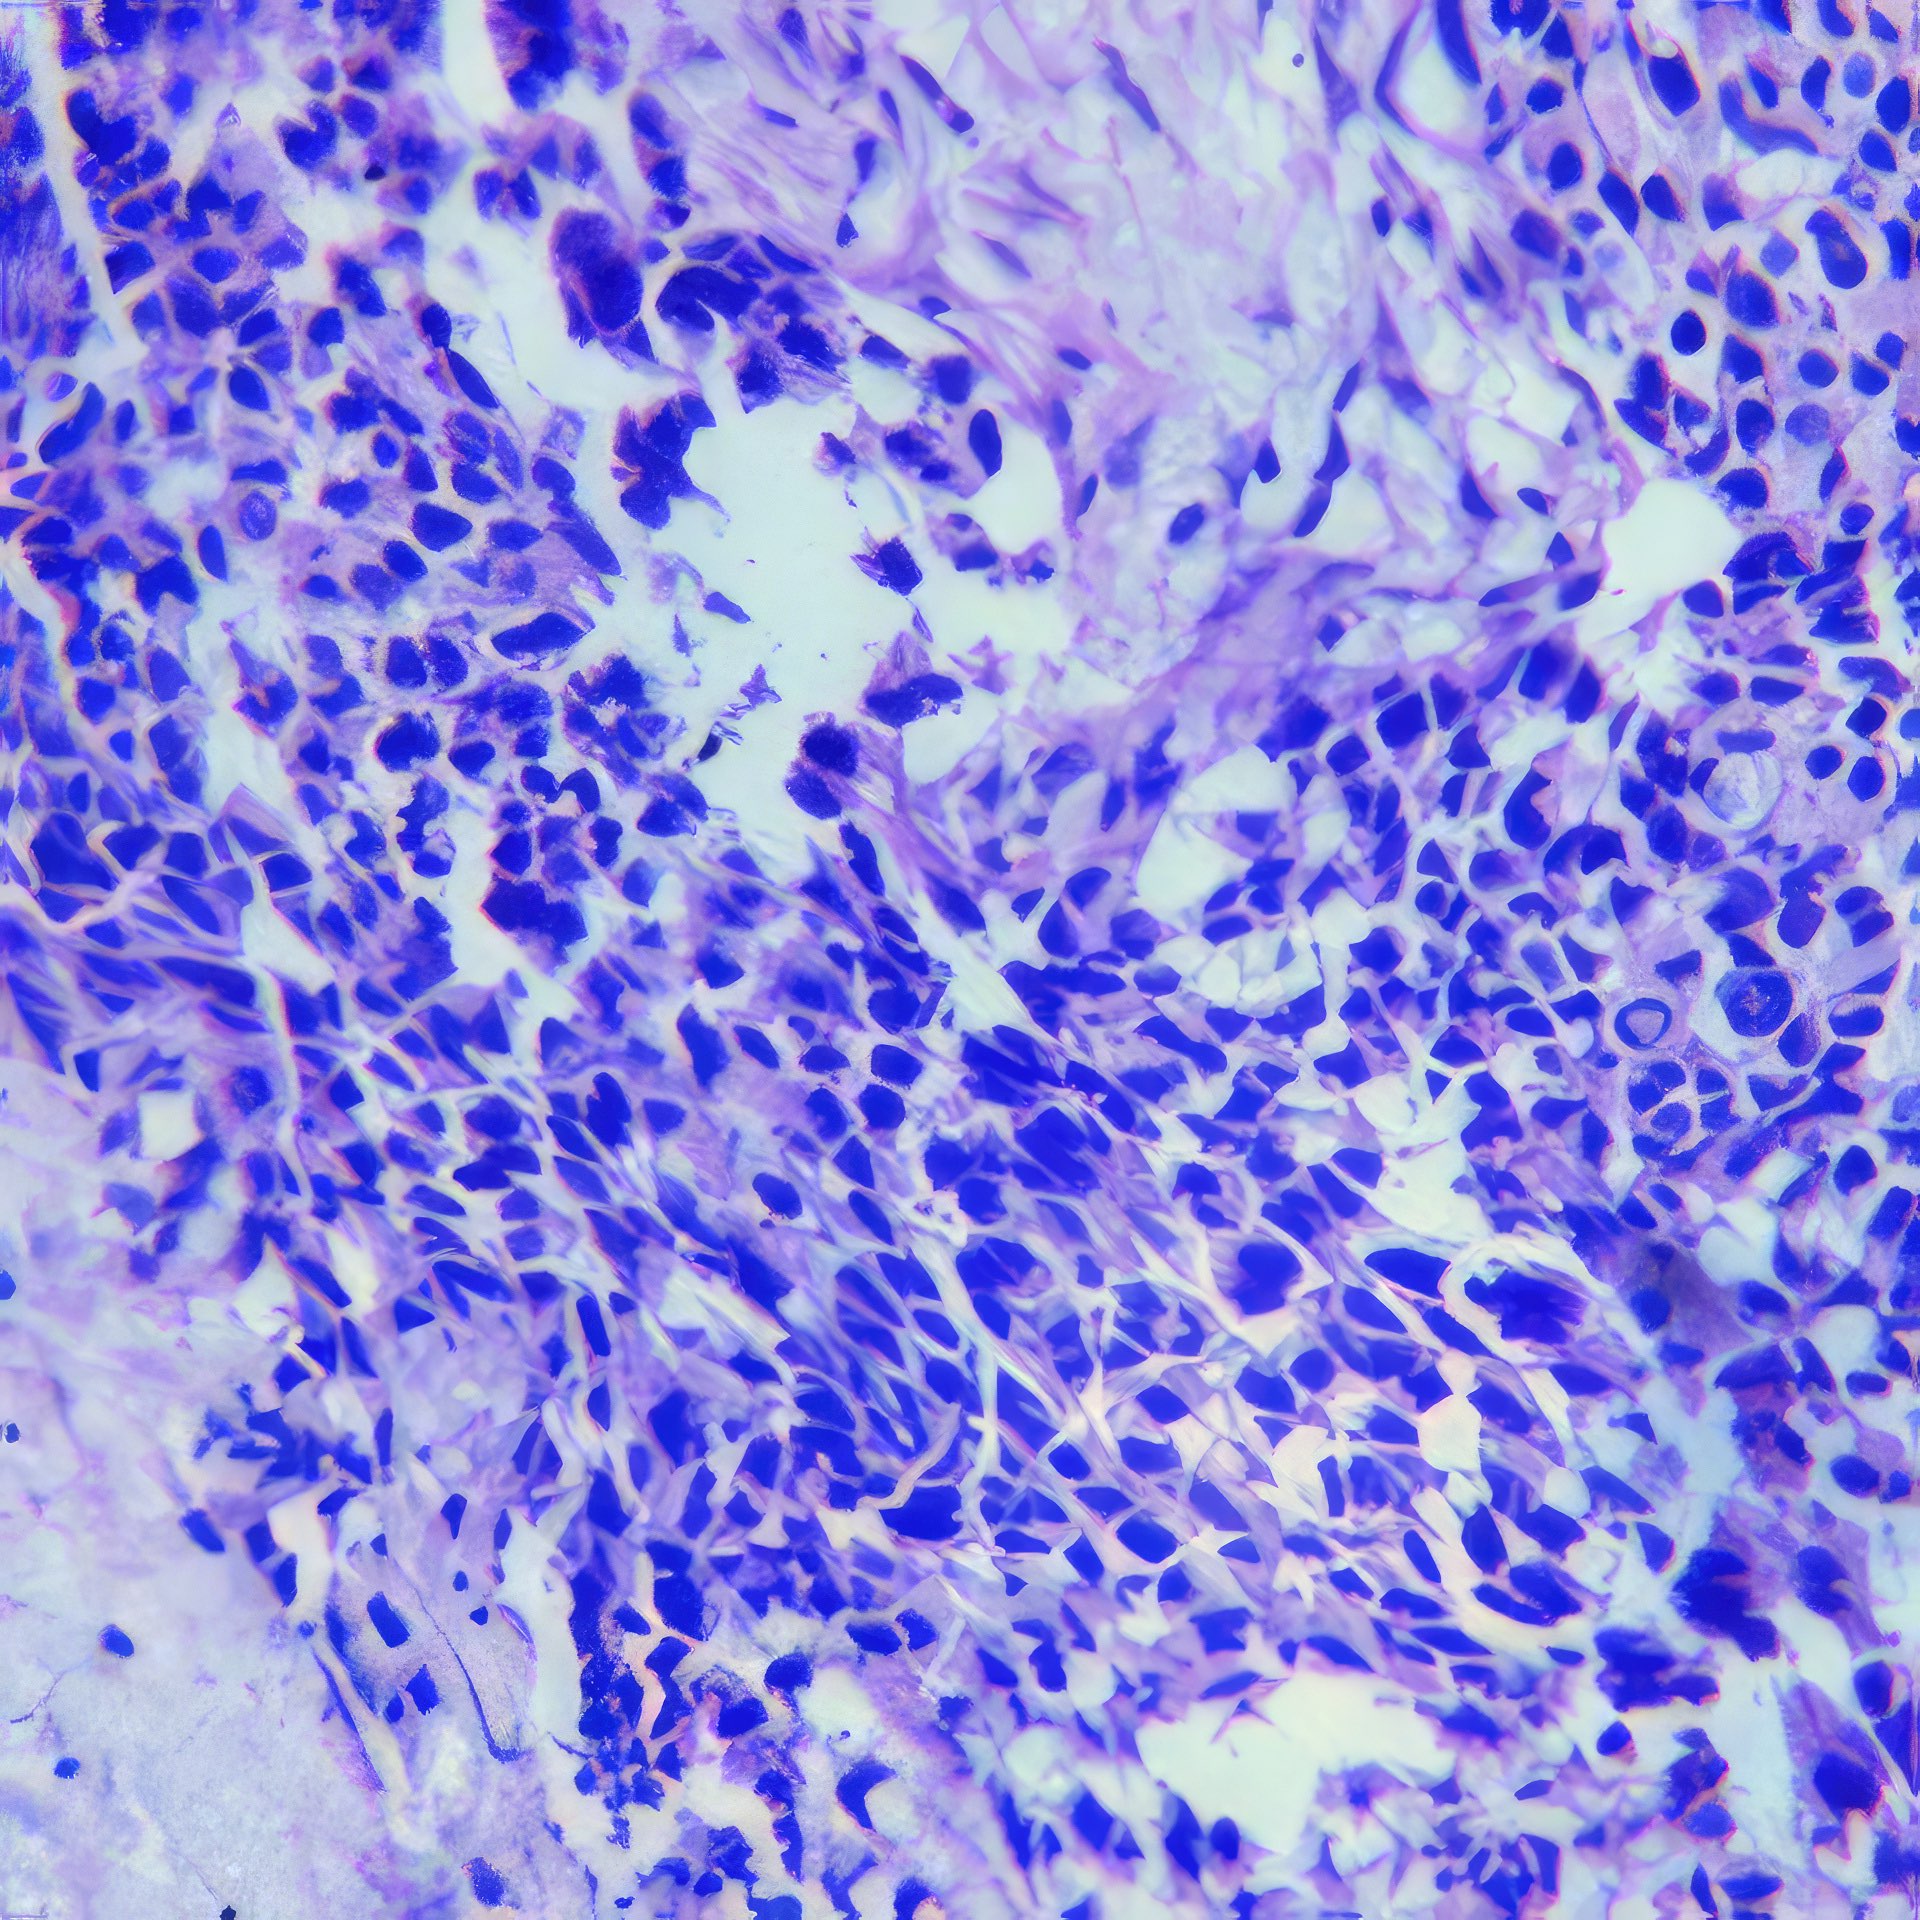

Abbildung 1 – 4: HE-Färbung; 1 – 4, original Obj. 40x, Abb. 4:

zusätzlich vergrößert

Die sich teils überlagernden Zellen erscheinen meist nacktkernig oder haben nur wenig Zytoplasma. Die Kerne variieren deutlich in Form und Größe, sind grob strukturiert und zeigen vereinzelt kleine Chromozentren und Protrusionen. Im Hintergrund etwas Zelldetritus.

Die histologischen Bilder (Abb. 1 und 2) bestätigen die zytologische Diagnose. Weite Teile des Gewebes sind durchsetzt von Tumorzellen, die nur angedeutet Verbände bilden und deutlich polymorphe Kerne aufweisen.

In diesem Fall bestand schon bei der klinischen Untersuchung kein Zweifel an der Karzinomdiagnose wegen eingezogener Brustwarze, oranger Hautfärbung und vergrößertem axillärem Lymphknoten, was klinisch nach WHO-Klassifikation T4bN1 entspricht. Die zytologische Diagnose eines Mammakarzinoms ist nicht immer so einfach. Dies gilt vor allem für das gut differenzierte tubuläre Karzinom, bei dem Größe und Form der Zellen nur schwer von normalen Zellen zu unterscheiden sind 12. Ähnliches gilt für das lobuläre Karzinom, dessen Zellkerne auch nur wenig in Form und Größe variieren; das auffälligste zytologische Merkmal ist die auch im zytologischen Präparat teilweise nachweisbare Indianfile-artige Anordnung 3. Die Trefferquote professionell durchgeführter FNA liegt knapp über 90%. Mag auch die Trefferquote der Dicknadel-Biopsie noch um wenige Prozent höher sein 4, so bietet die FNA besonders in unterversorgten Ländern den Vorteil, dass die Herstellung der Präparate einfacher, billiger und weniger zeitaufwendig ist.

Abbildung 1 und 2: Histologische Bilder desselben Falles, HE-Färbung, Abb.1: Obj. 10x, Abb. 2: Obj. 20x